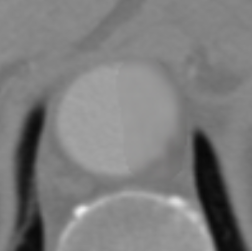

Figure 9 shows axial CTA images of an aortic dissection case. In both rows of this figure an example for executing an inpainting with the inpainting tool is given. The image section of all sub-figures is equal to the defined region of interest. The sub-figures in Figure 9 show from left to right: unedited CTA scan showing the aorta and surroundings, the mask used for the inpainting and the inpainting result. The Sub-images (a) and (b) include a dissected aorta, whereas the dissection is removed in the sub-images (d) and (f).

(d) Original image

(e) Masked image

(f) Inpainting result

Figure 9: Two examples for an inpainting of an aortic dissection utilizing the inpainting tool.

Looking at the results presented in Figure 9, one can see that the depicted dissected aorta is successfully changed to a healthy looking aorta. But it is also noticeable, that the region reconstructed by the inpainting is slightly blurred, which could be addressed by refinement of the EdgeConnect model. The timing analysis in section 6 shows that a call of the inpainting tool is completing in around four seconds, wherein the majority is caused by executing the neural network. This indicates the code of the inpainting tool itself offers little room for speeding up the application.